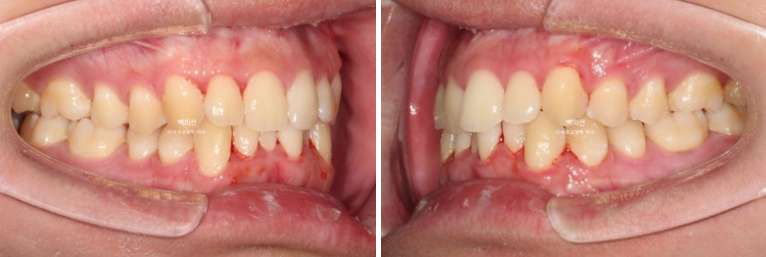

25.02~25.08

아래 앞니의 배열 개선이 드라마틱 하네요. 안으로 쓰러진 작은어금니들 배열도 좋습니다.

교정 후 아래 앞니 잇몸 라인 높낮이가 자연스럽게 맞아진 것이 보입니다.

치아 높이가 교정으로 맞아지면 잇몸라인은 자연스럽게 맞아집니다.